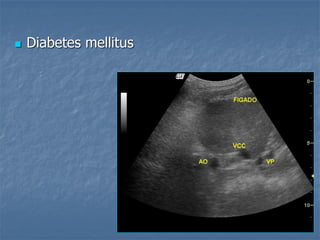

 Diabetes mellitus